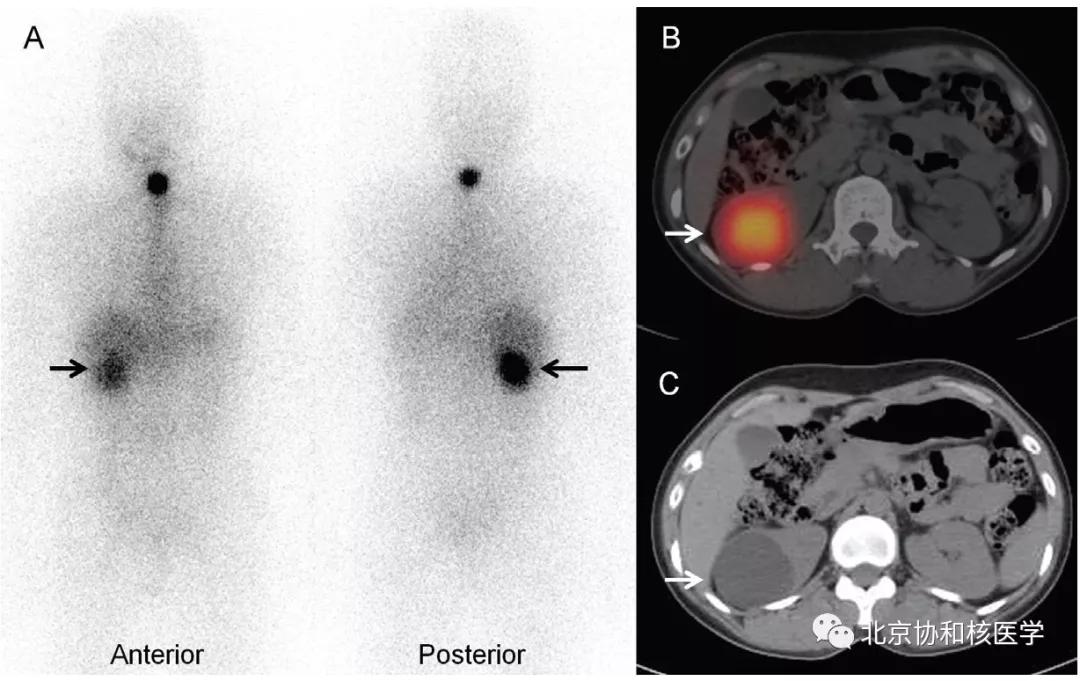

肝周或肝被膜下囊肿所致碘摄取:

单纯肾囊肿的碘摄取,可能由于囊液与集合系统的交通或碘通过囊肿上皮细胞分泌入囊内滞留形成: